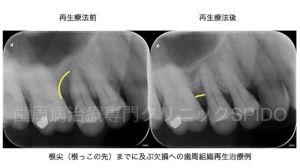

歯周病治療専門クリニックSPIDO院長の辻翔太です。 当院では、歯周病で失われた組織の再生、インプラ ...